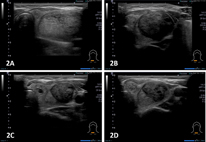

針對頸部良性囊腫,如甲狀腺囊腫等,醫師會用超音波導引將囊液抽出消腫,並加以細胞檢查。有的患者抽了很多次仍然反覆腫脹,這時候除了手術將良性囊腫切除外,也可使用超音波導引注射硬化藥劑治療。本院特地引進99.5%藥用無水酒精為患者進行硬化治療,過程就像一般囊腫引流;在引流最後時將少量酒精注入囊腫內,治療後病患並不會酒醉,但部分患者可能有1至2天腫脹及疼痛的現象,慢慢使囊腫消腫(圖一為99.5%藥用無水酒精治療前後超音檢查圖片變化),約有八成以上的囊腫可以經由1次的注射後獲得緩解。本院申請健保給付,於2021年12月獲得健保通過使用於復發性之甲狀腺良性囊腫;至於沒有獲得健保給付的其他良性囊腫,我們也申請新北市衛生局的自費注射且獲得同意。我們這項治療成果也在2021年獲得中華民國超音波醫學會超音波優秀論文第一名的殊榮。

圖一、超音波導引酒精注射成效(1A、酒精注射前;1B、注射後一個月追蹤;1C、注射後三個月以上追蹤;1D、注射後半年以上追蹤)